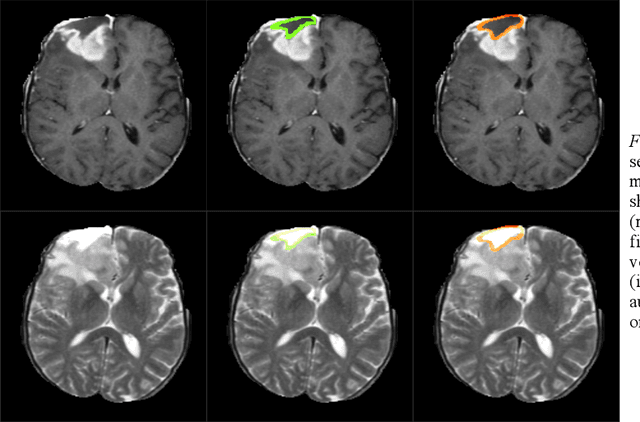

Abstract:In this work, we compare five deep learning solutions to automatically segment the resection cavity in postoperative MRI. The proposed methods are based on the same 3D U-Net architecture. We use a dataset of postoperative MRI volumes, each including four MRI sequences and the ground truth of the corresponding resection cavity. Four solutions are trained with a different MRI sequence. Besides, a method designed with all the available sequences is also presented. Our experiments show that the method trained only with the T1 weighted contrast-enhanced MRI sequence achieves the best results, with a median DICE index of 0.81.